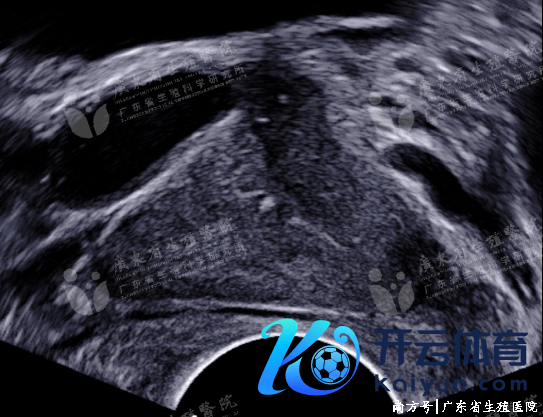

获取性射精管梗阻

获取性射精管梗阻成分主要见于泌尿生殖说念感染导致射精管粘连、短促,管壁及腔内形成钙化或结石,酿成射精管梗阻。射精管炎症性梗阻声像施展为射精管慢性炎症改造,射精管管壁回声增粗、增强,梗阻近端射精管不同进度彭胀或囊肿形成,沿管壁可见黑点状强回声钙化及中等回声附壁结节。射精管全皆梗阻可致同侧精囊囊状彭胀,输精管及附睾管不同进度彭胀。

射精管炎性梗阻